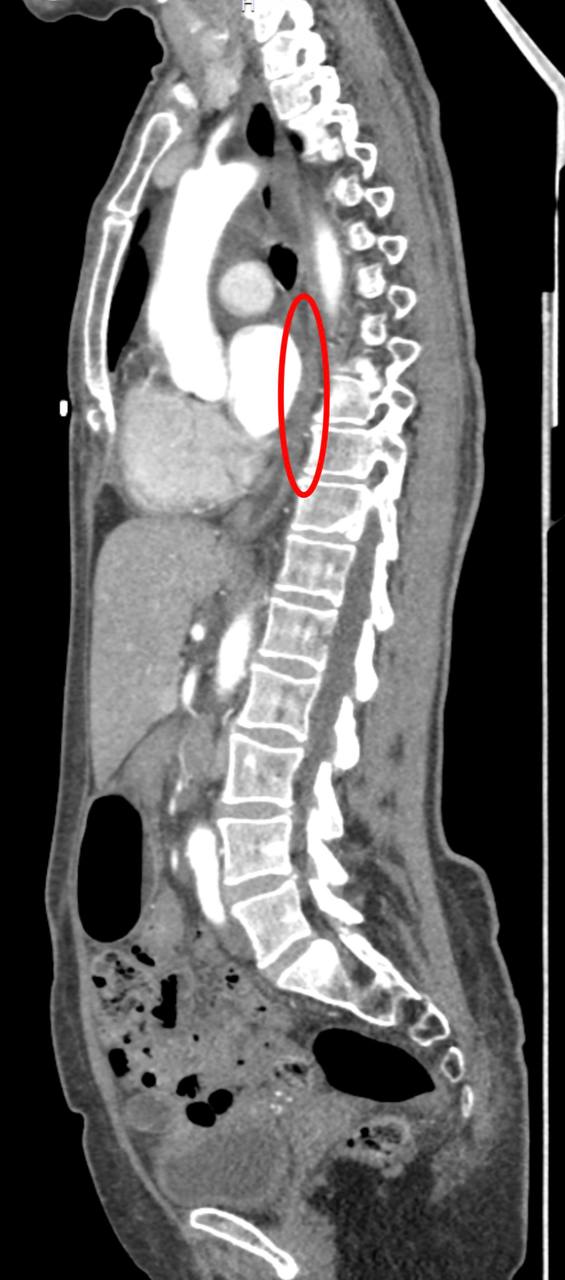

Хирурги провели торако-лапароскопическую субтотальную резекцию пищевода типа МакКеона с лимфаденэктомией и одновременную правостороннюю гемиколэктомию с удалением поражённого участка ободочной кишки. Новый пищевод врачи сформировали из желудка пациентки.

«Хирургия действительно сложная, потому что мы работали в трёх анатомических зонах: в груди, в животе и на шее», — рассказал заведующий хирургическим отделением клиники Сергей Осминин.